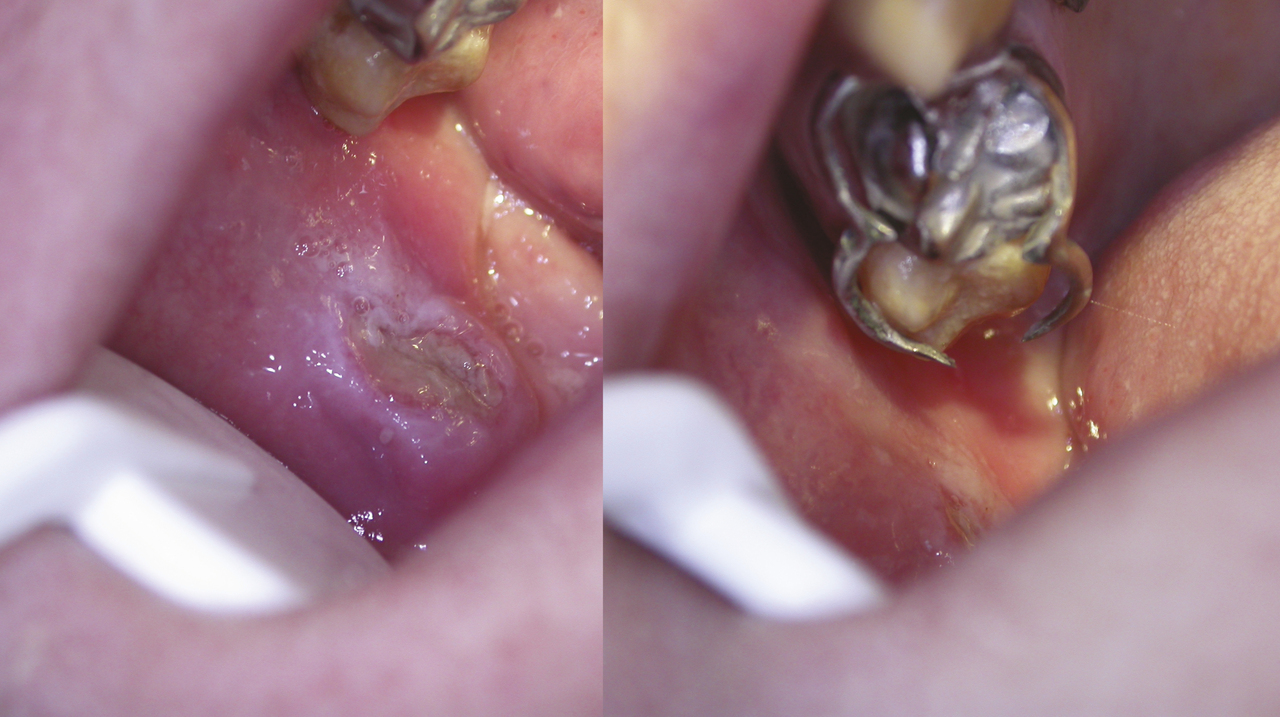

Un aphte « géant » est défini par un diamètre supérieur à 1 cm (fig. 2) ; c’est une forme sévère extrêmement douloureuse pouvant demander plusieurs semaines voire plusieurs mois pour cicatriser en l’absence de traitement. Peu fréquente, elle est généralement liée à une immunodépression (infection par le VIH).

Une ulcération ne correspondant pas à la description ci-dessous ou l’absence de cicatrisation spontanée sous 2 à 3 semaines doivent alerter. Les diagnostics différentiels sont nombreux (tableau). Attention à ne pas méconnaître un carcinome épidermoïde débutant (fig. 3). Le diagnostic précoce d’une lésion potentiellement maligne est encore le meilleur moyen d’appliquer suffisamment tôt le traitement pour éviter l’évolution vers ce cancer dont le pronostic à 5 ans reste sombre, autour de 40 % de survie.

Ulcération traumatique

L’ulcération traumatique est souvent unique, de taille variable, douloureuse à fond fibrineux et à bordure blanchâtre. Elle est souple, ne s’accompagne pas d’adénopathie satellite. L’agent traumatisant est souvent évident : carie, couronne dentaire défectueuse, prothèse inadaptée ou crochet blessant (fig. 4) ; sa suppression permet la cicatrisation en une dizaine de jours.